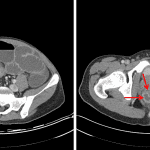

- Peripherally-enhancing perirectal fluid and gas collections measuring 3 x 2 x 1 cm on the right, 1 x 0.7 x 0.5 cm more anteriorly on the right, and 1.5 x 1 x 0.5 cm on the left

- Enterocolonic fistula bridging the terminal ileum and sigmoid colon and adjacent enteroenteric fistula

- Crohn disease with small bowel obstruction, fistulas, and abscesses

Findings concerning for active inflammatory bowel disease (most consistent with Crohn disease) with segmental inflammation of the terminal ileum and distal colon and rectum. Associated upstream small bowel distension, enteroenteric and enterocolonic fistulas, and pericecal and perirectal abscesses.